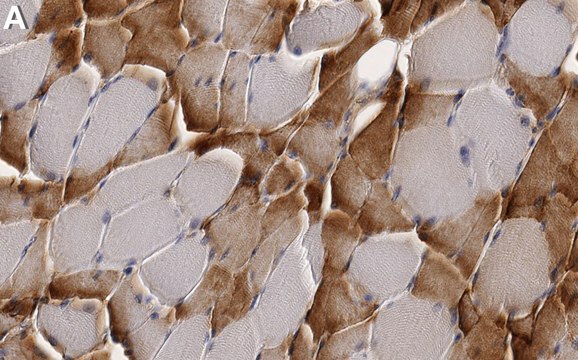

Immunohistochemistry (Paraffin) Analysis: A 1:100 dilution from a representative lot detected SLC16A3/MCT4 in human skeletal muscle tissue sections.